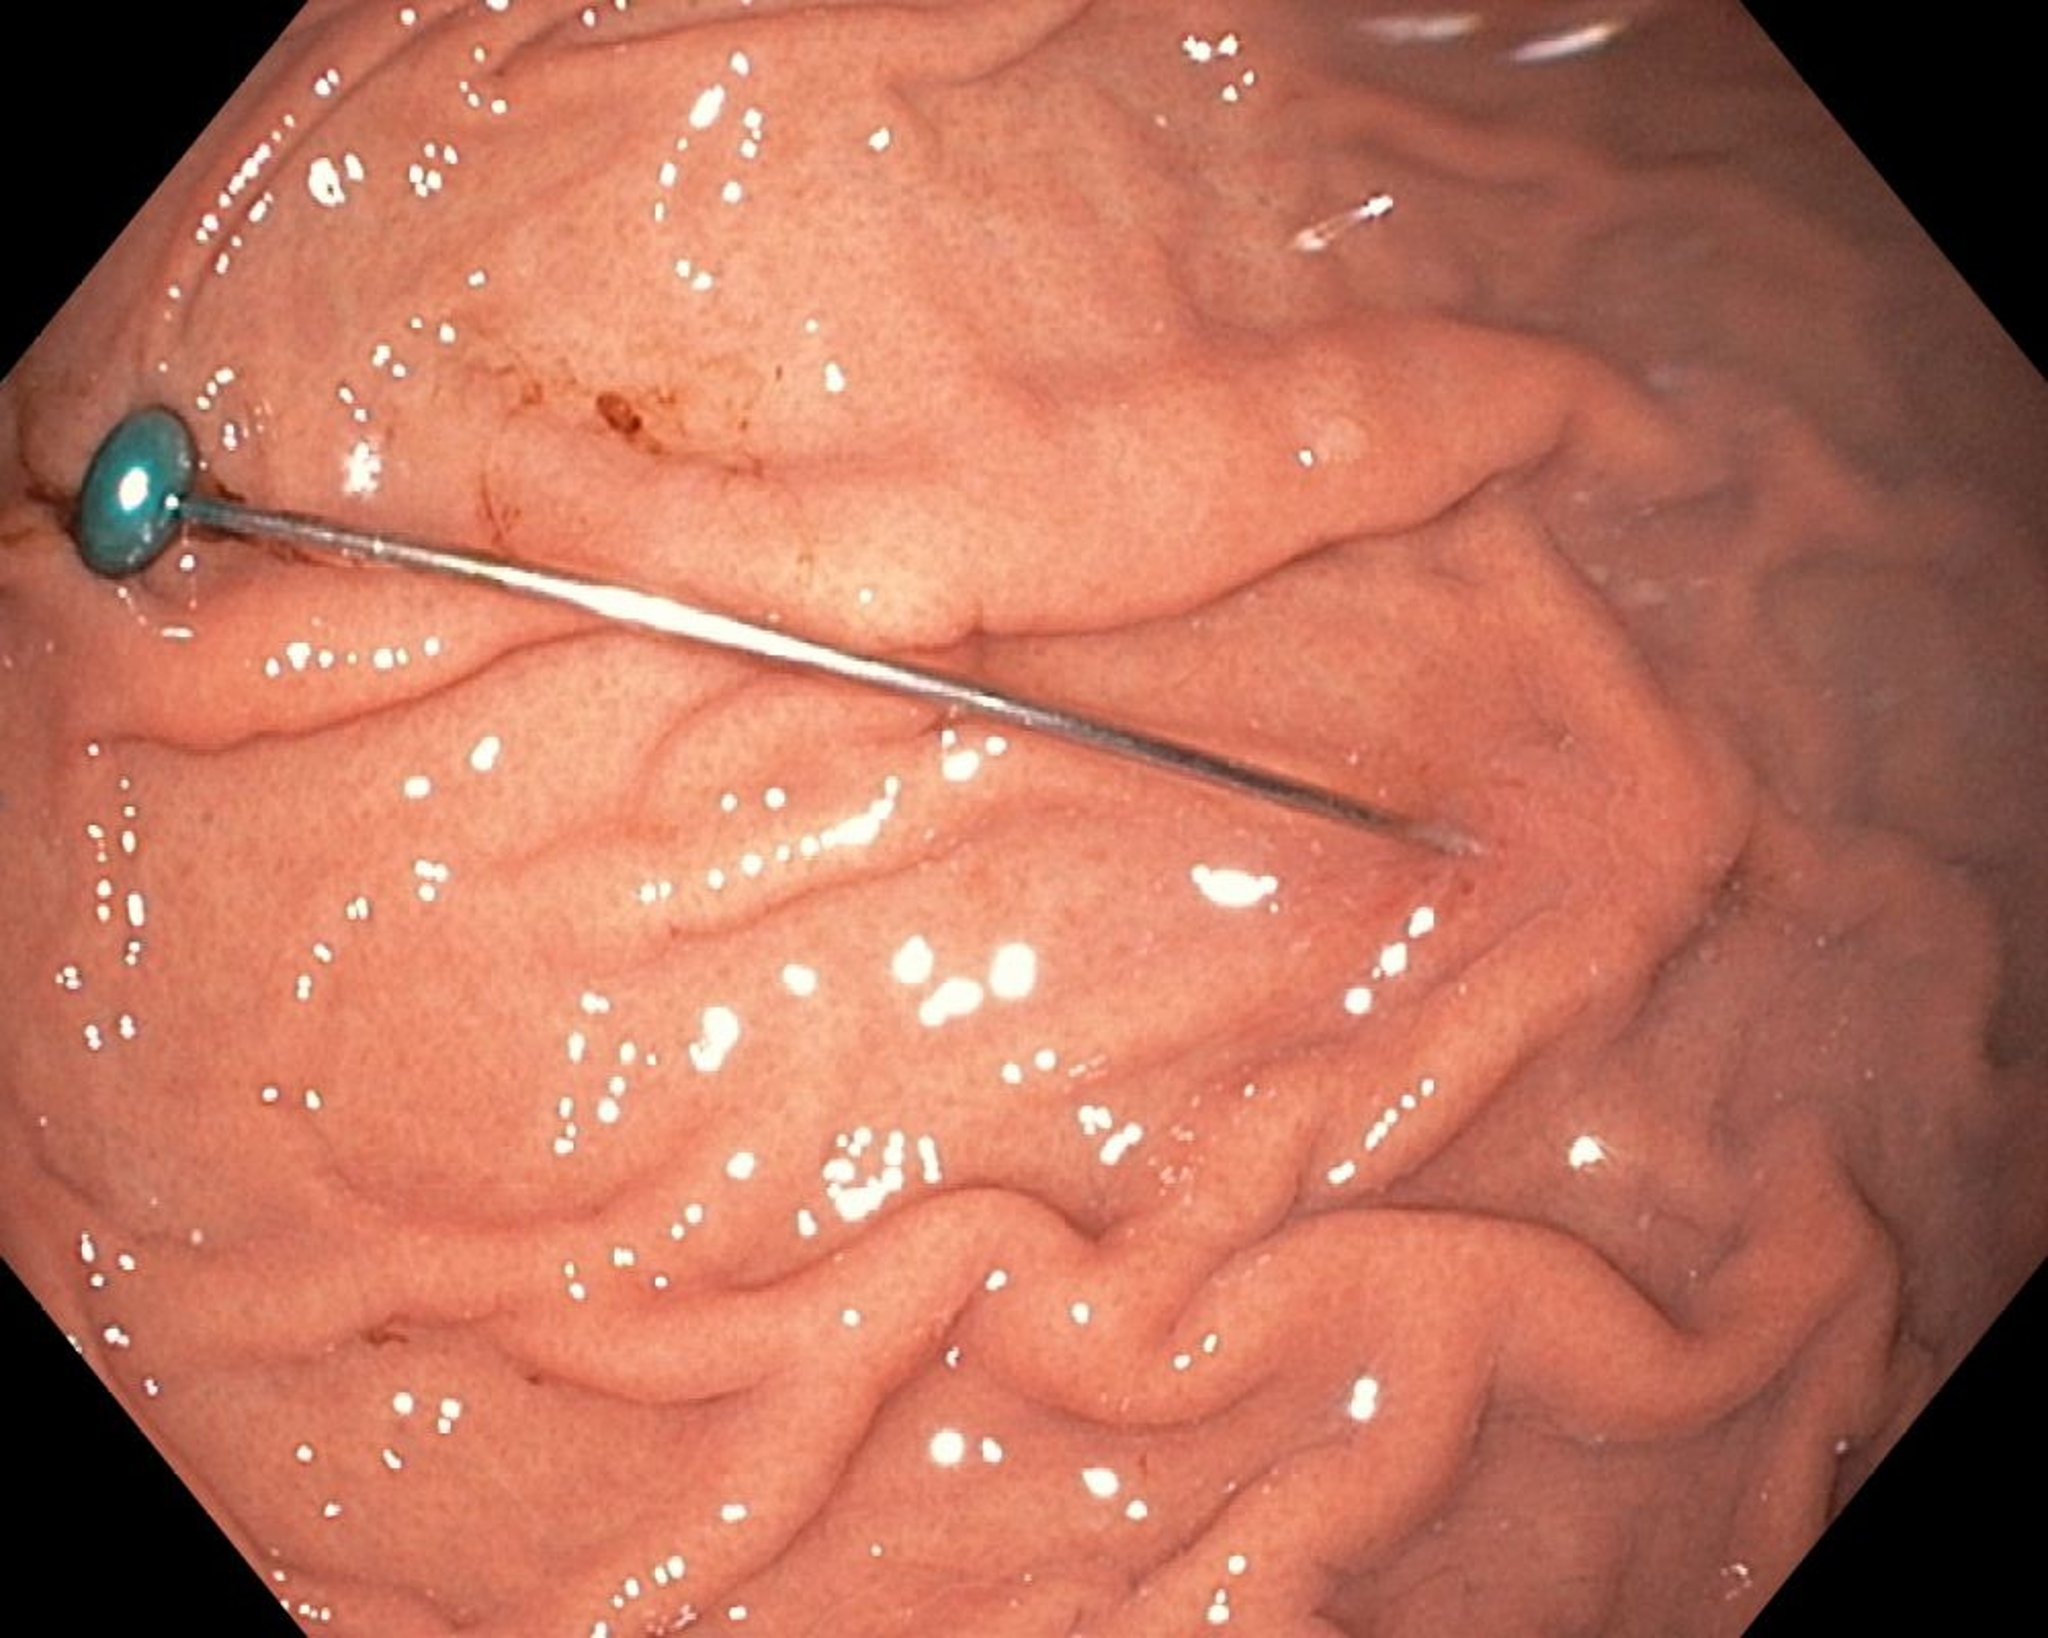

Corps étranger dans l'estomac (endoscopie)

Cette image endoscopique montre un corps étranger pointu dans l'estomac.

Image fournie par Uday Shankar, MD.